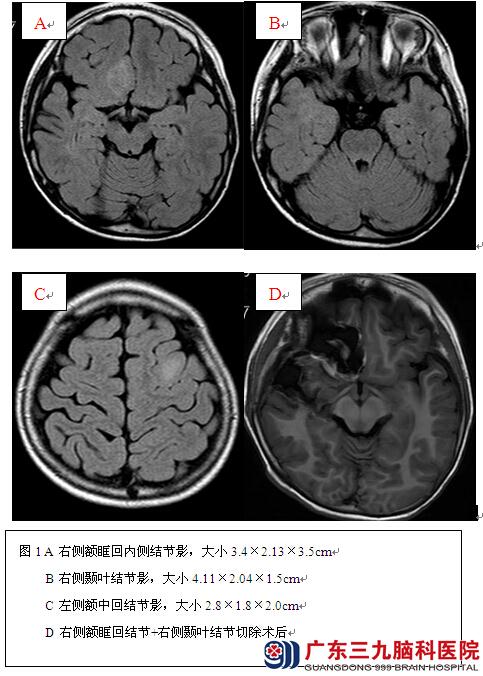

辅助检查:头颅MR示右侧额底、左侧额叶、右侧颞叶内侧多发异常信号影(具体见图1)。头颅CT示室管膜下钙化结节影。PET示右侧额叶底面、右侧颞叶及右侧顶叶多发低代谢区(见图2);VEEG示发作间期各脑区见癫痫样放电,以右侧前头部著;发作期为右侧前头部起源的部分性发作(见图3)。心脏彩超、腹部彩超:无异常。韦氏智力测试:言语智商50,操作智商57,全量表智商49;韦氏记忆测试:9分。